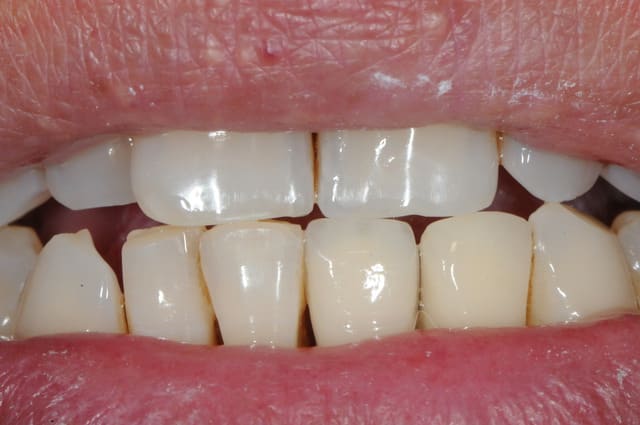

je me permet de ressusciter ce poste car j'ai placé la prothèse il y a un mois.

photo 1: début du cas

photo 2: fin d'intervention

photo 3: j+3mois

photo 4 +5: prise d'empreintes

photo 6-7-8-9: couronne finie.

merci de votre attention :)

PS: le patient ne veux pas faire celle d'à coté.

grr, moi ça me démange...